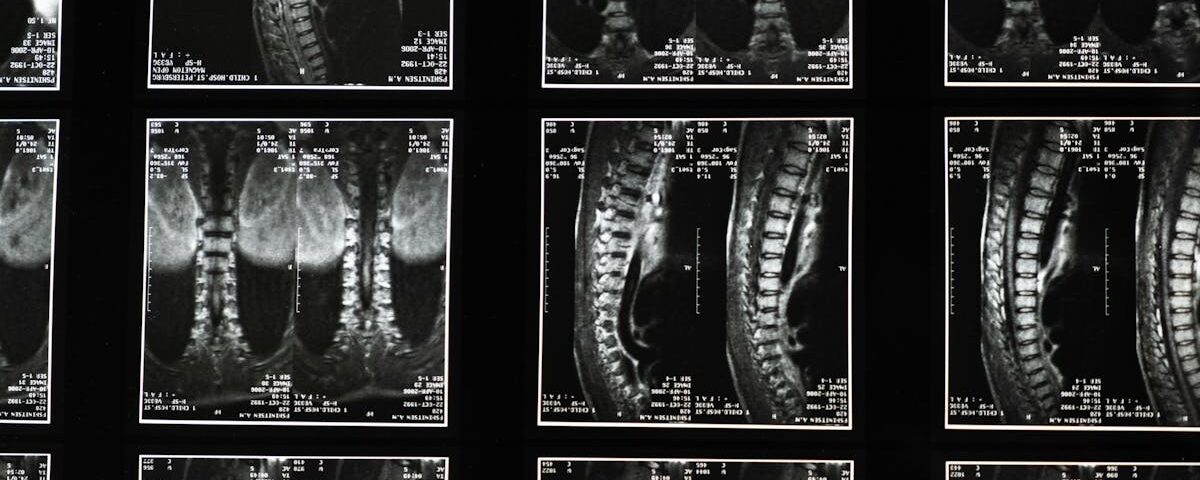

Une IRM ou une radiographie est généralement recommandée pour évaluer l’état de la colonne vertébrale.